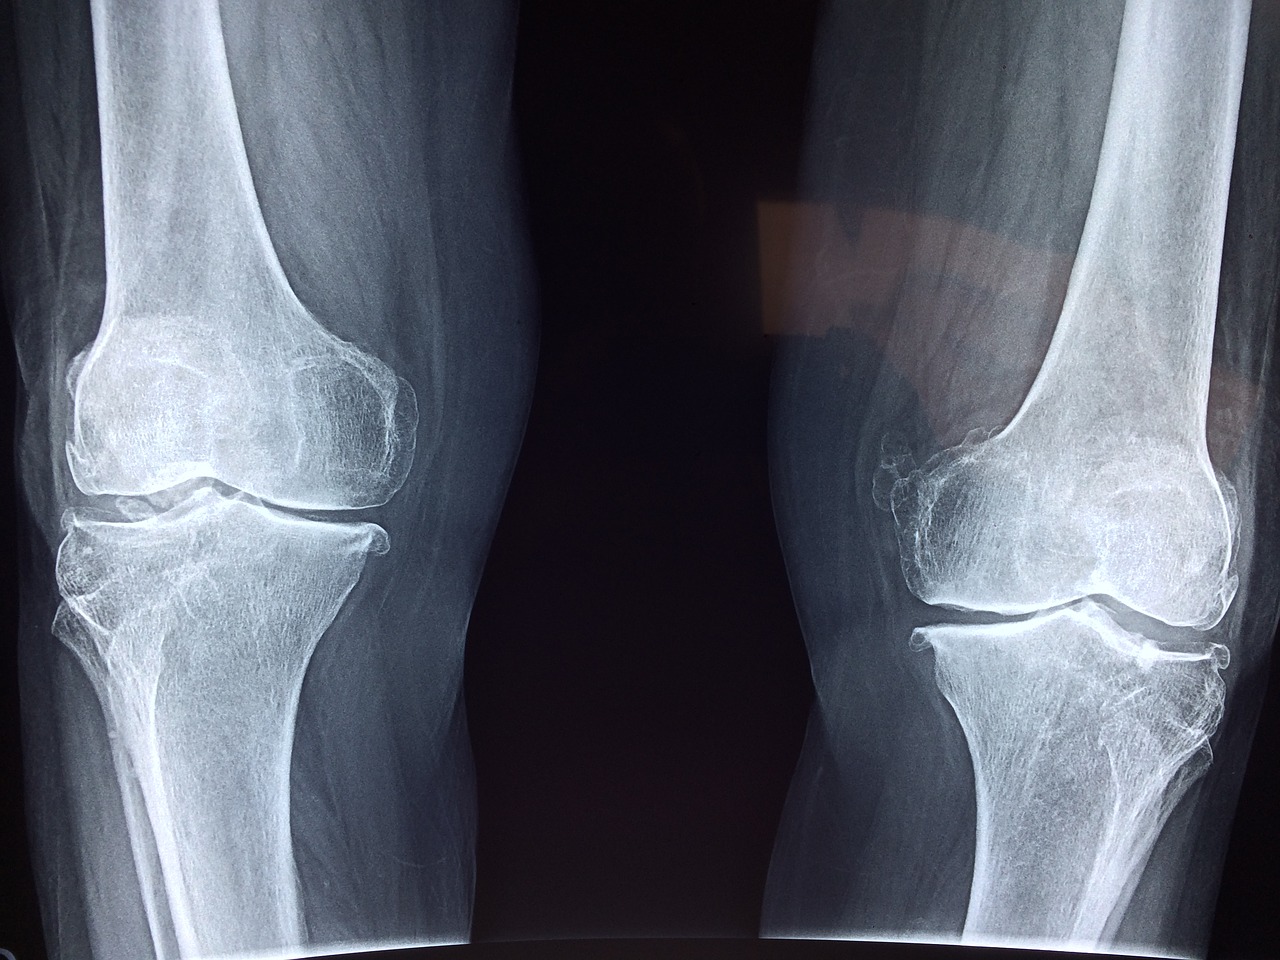

- Pomaga usunąć „piasek” z dróg moczowych i stawów, łagodzi bóle stawów i mięśni oraz eliminuje kaszel i flegmę.

- łagodzenie bólu stawów,

Skrzyp polny to roślina o wszechstronnym działaniu, korzystnym nie tylko dla układu moczowego, ale także dla zdrowia naczyń krwionośnych. Dzięki swoim właściwościom, poprawia elastyczność naczyń i zapobiega ich stwardnieniu, co wpływa pozytywnie na przepływ krwi i pomaga szybciej usuwać szkodliwe substancje z organizmu. Dodatkowo, skrzyp polny może być pomocny w przypadku chorób takich jak dna moczanowa, reumatyzm, żylaki czy stany zapalne. Jest również skutecznym środkiem w leczeniu bólu gardła.

- Po tym czasie namocz w roztworze grubej gazy i przyłóż na bolące miejsca, np. plecy, pięty czy kolana, przed snem.

Zakryj miejsce przy pomocy folii i owiń, aby nie pobrudzić pościeli. Pozostaw na całą noc, upewniając się, że miejsce pozostaje ciepłe. Wykonuj to przez kolejne 3 noce. Osobiście odczuwałam ból w dolnej części pleców, jednak zaskoczyło mnie, że już po pierwszej nocy ból ustąpił, a po trzeciej zniknął całkowicie. Nawet najskuteczniejsze maści ze sklepu nie były w stanie mi pomóc w taki sposób. Gorąco polecam tę sprawdzoną recepturę z naturalnej apteki wszystkim.